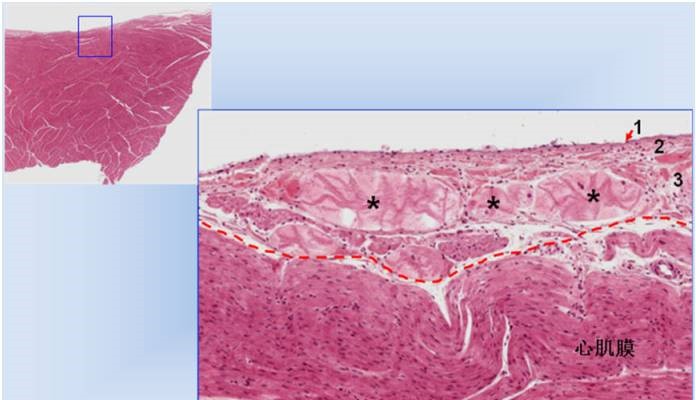

图7. 心壁光镜像,示心内膜和心肌膜。

高倍镜见心内膜分为三层:内皮(1),内皮下层(2)和心内膜下层(3)。心内膜下层中可见浦肯野纤维(*),为特殊的心肌纤维,是心脏传导系统的分支。